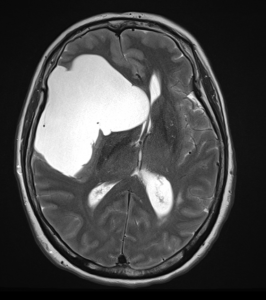

Η μαγνητική εγκεφάλου ανέδειξε ευμεγέθη αραχνοειδή κύστη δεξιά κροταφικά με σημαντική πίεση επί του υγιούς εγκεφάλου και παρεκτόπιση των δομών της μέσης γραμμής (έμμεση ένδειξη αυξημένης ενδοκράνιας πίεσης).

Στη συγκεκριμένη περίπτωση όμως η κύστη ήταν εξαιρετικά μεγάλη και πίεζε σημαντικά τον παρακείμενο εγκέφαλο. Αυτό φαίνεται ξεκάθαρα από τη λεγόμενη “παρεκτόπιση των δομών της μέσης γραμμής”. Αυτό σημαίνει ότι ο εγκέφαλος πιέζεται από τη μία μεριά τόσο πολύ, που οι φυσιολογικές εγκεφαλικές δομές παρεκτοπίζονται. Επιπλέον, η αυξημένη ενδοκράνιος πίεση προκάλεσε οίδημα στα οπτικά νεύρα, γι’ αυτό και η ασθενής είχε προβλήματα με την όρασή της.